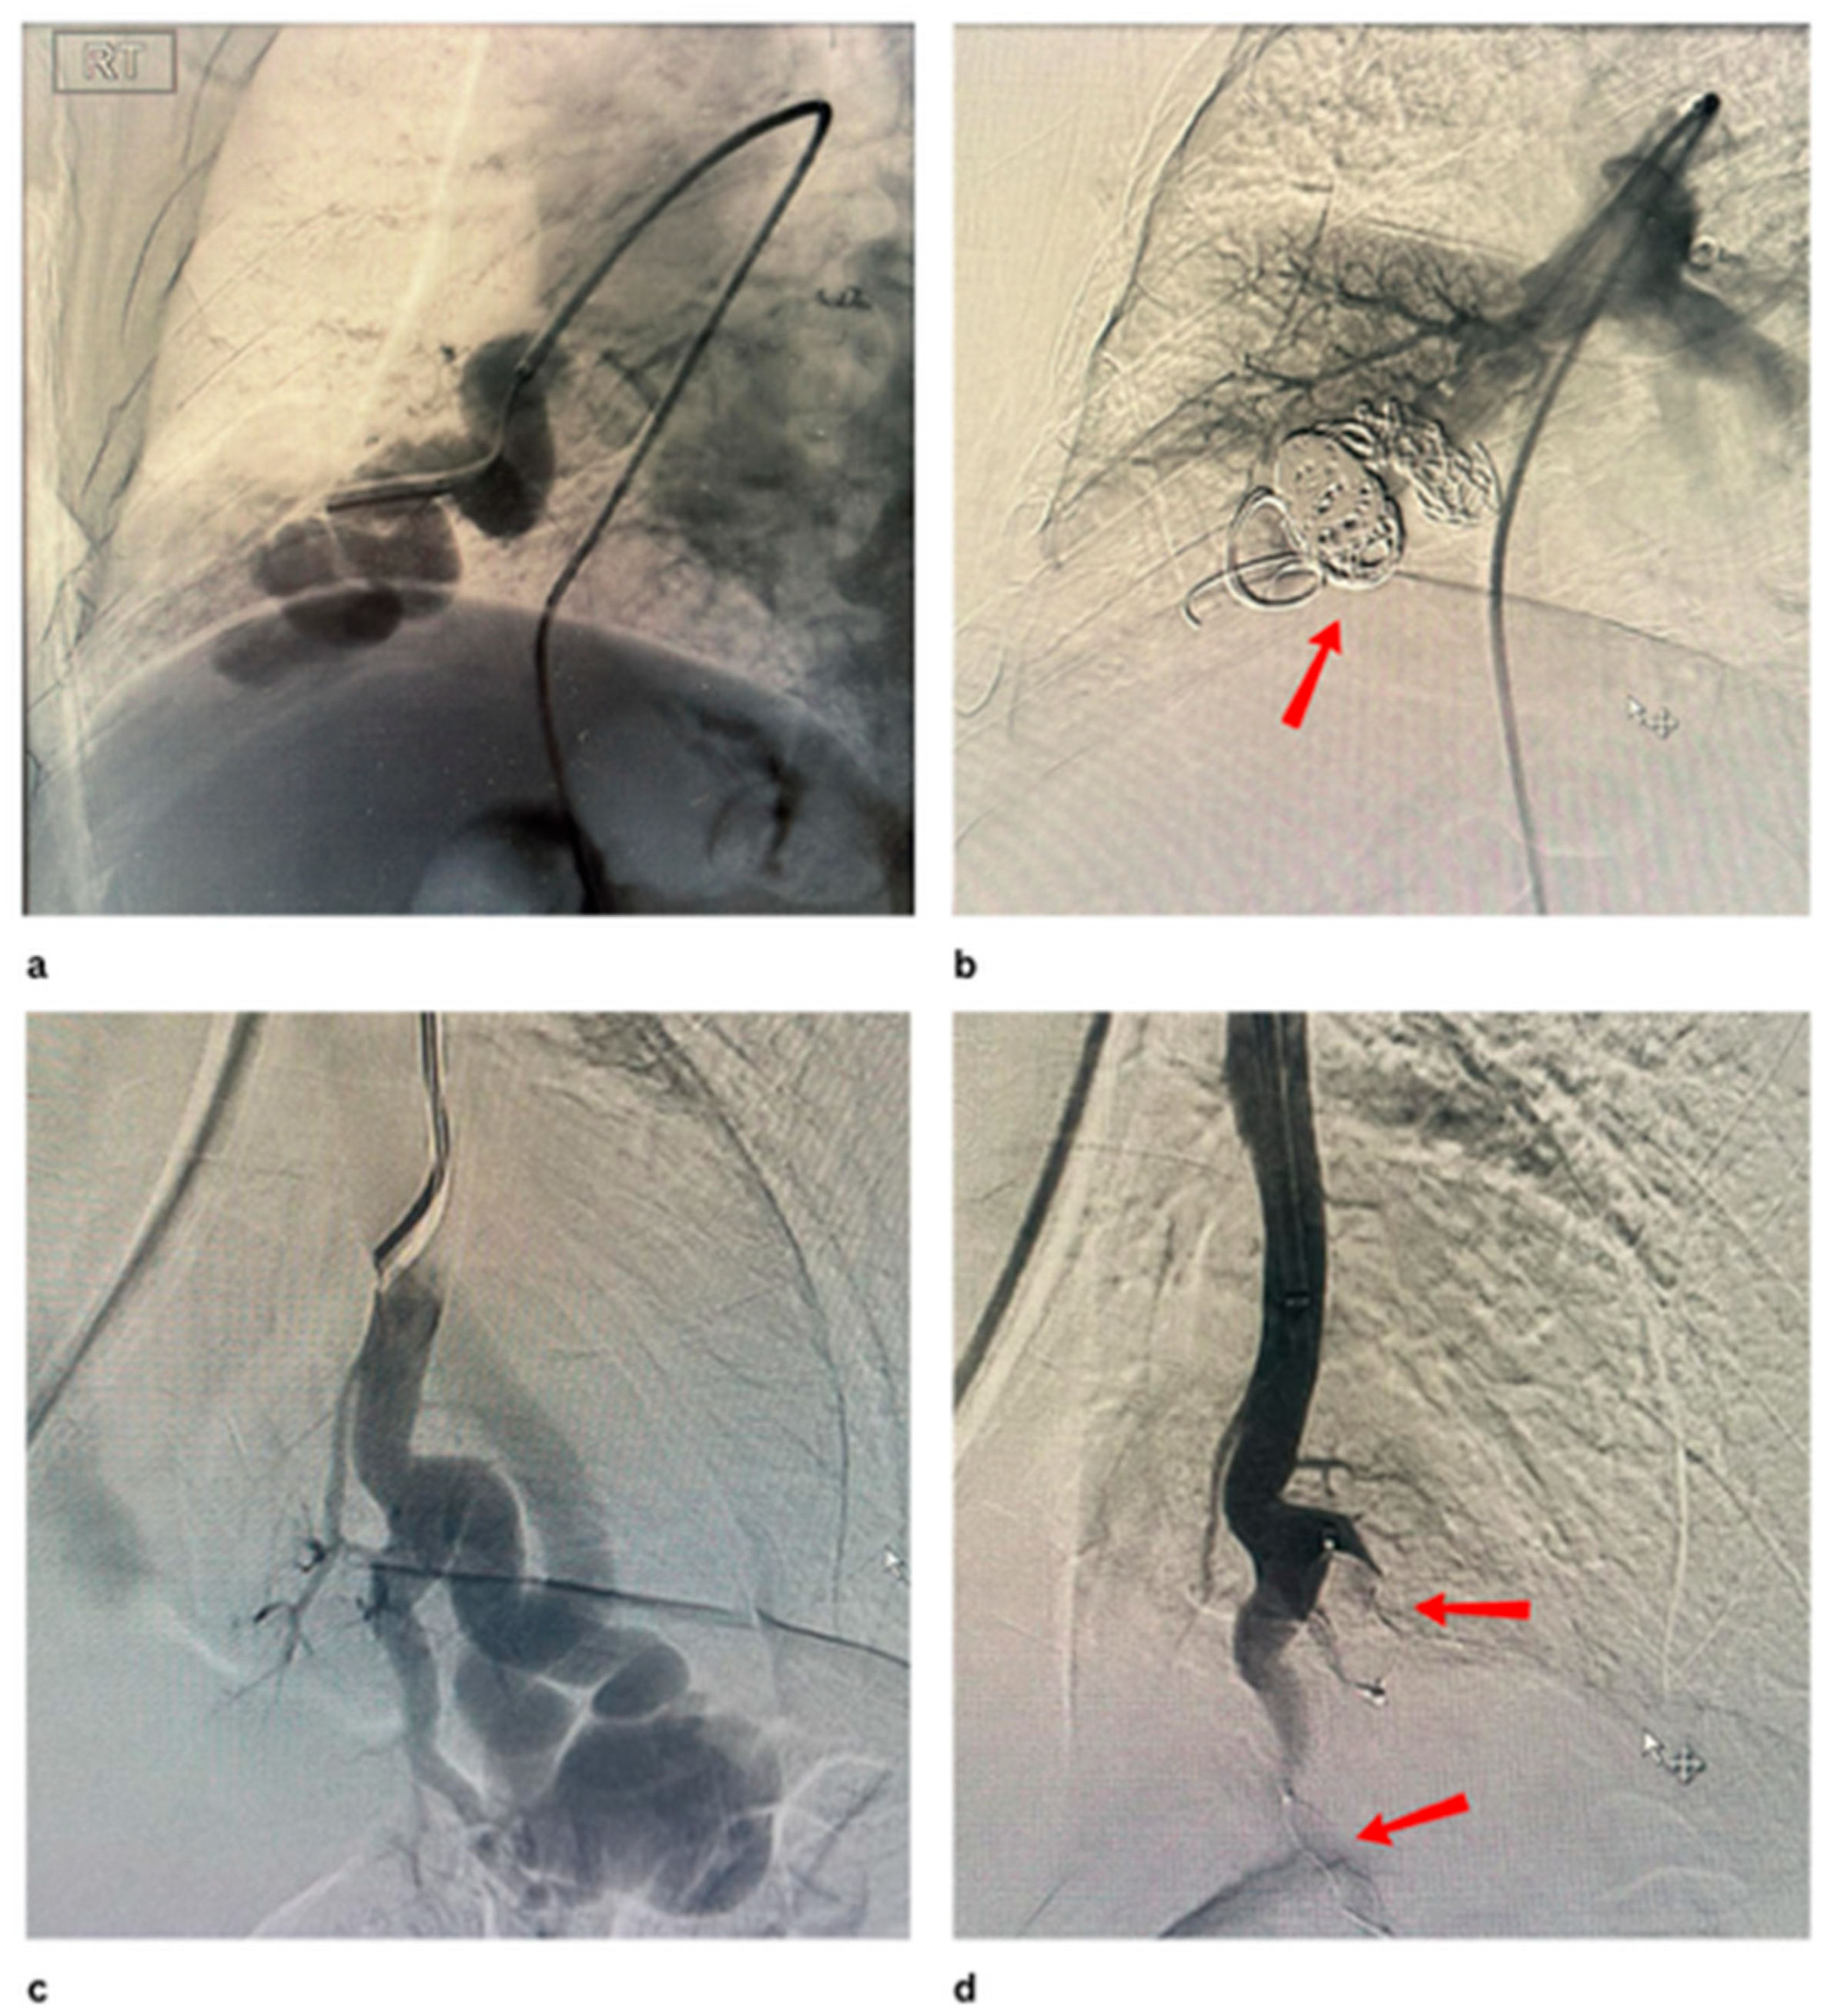

- Prasad, S.N.; Sharma, S.; Singh, V.; Phadke, R.V. Endovascular management of pulmonary arteriovenous malformations presenting as multiple brain abscesses. BMJ Case Rep. 2022, 15, e251593. [Google Scholar] [CrossRef] [PubMed]

- Greben, C.R.; Setton, A.; Putterman, D.; Caplin, D.; Lenner, R.; Gandras, E.J. Pulmonary Arteriovenous Malformation Embolization: How We Do It. Tech. Vasc. Interv. Radiol. 2013, 16, 39–44. [Google Scholar] [CrossRef]